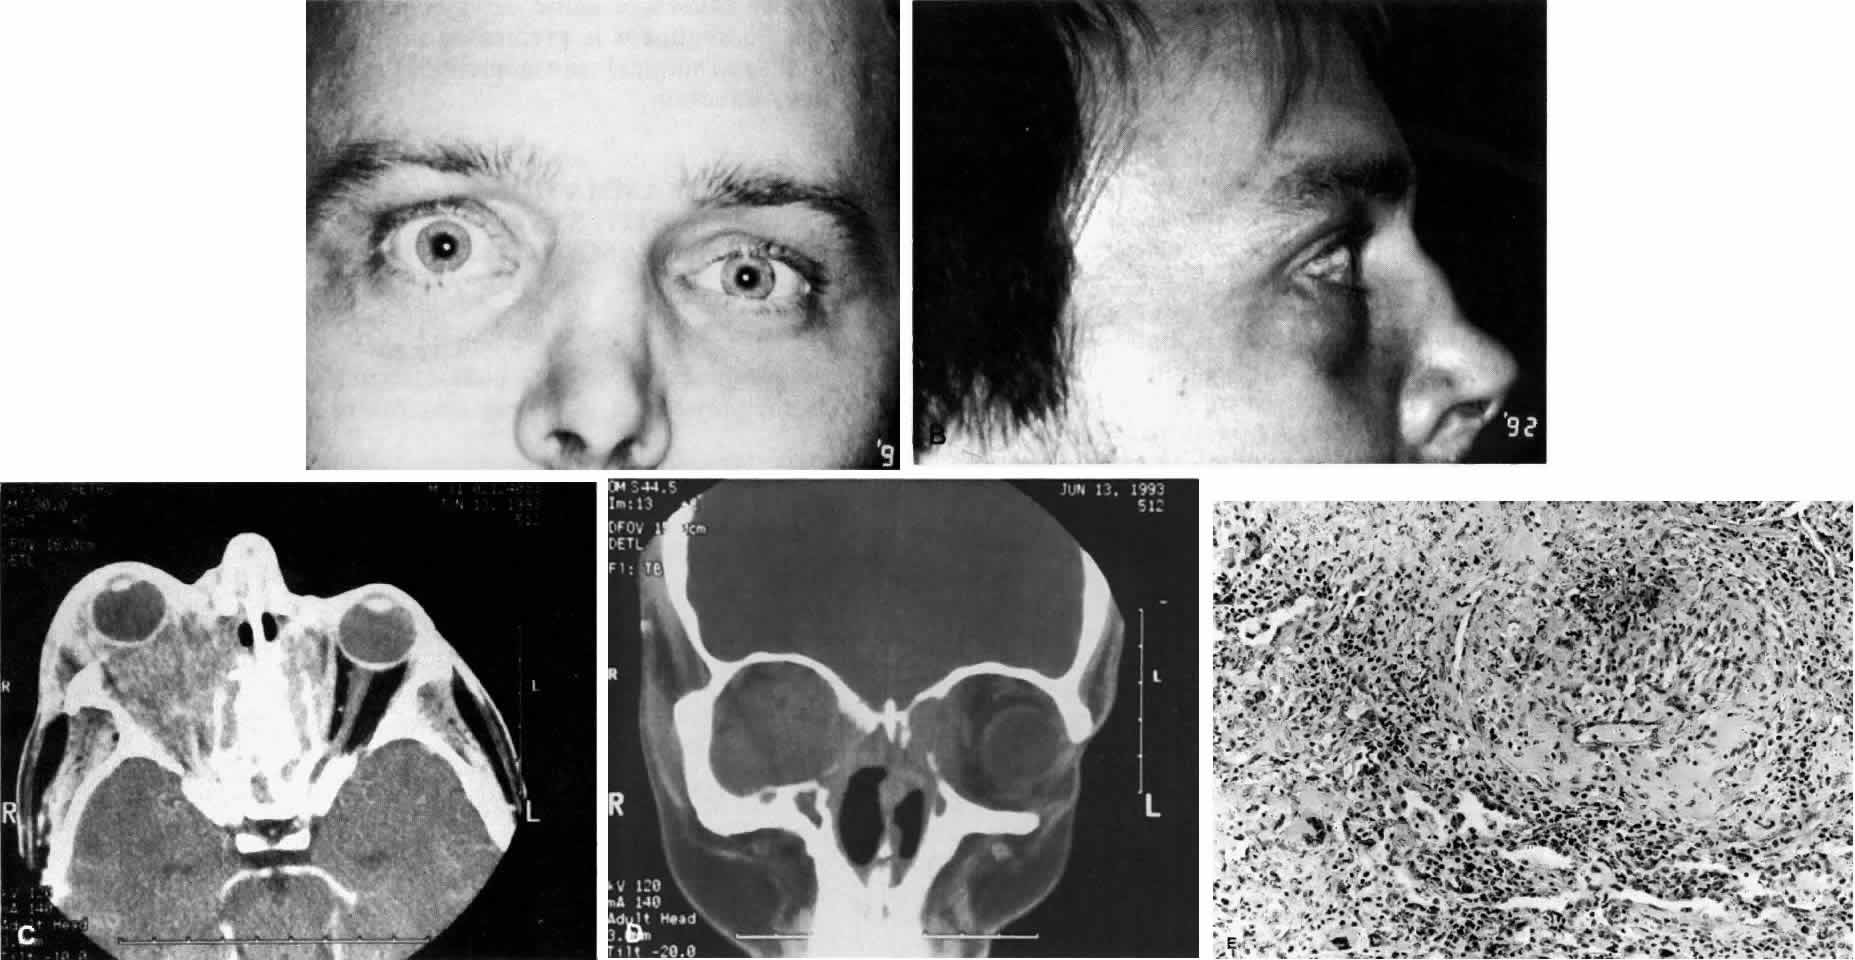

Fig. 11. A. This 31-year-old man has had Wegener's granulomatosis for 2 years. His disease process is stable on chronic corticosteroid therapy. He has no evidence of systemic disease. Note right-sided proptosis and hyperglobus. B. Profile of same patient demonstrating collapse of nasal bridge from bony destruction secondary to Wegener's granulomatosis. Note presence of swelling in lower eyelid. C. Axial CT image from the same patient demonstrating significant bilateral disease and bony destruction. Despite the extent of the orbital process on the right, the patient does not have diplopia. D. Coronal CT image showing destruction of medial orbital walls, vomer, and orbital septum. E. Pulmonary biopsy specimen from patient with orbital signs contains an almost obliterated vessel to right of center and scattered giant cells on left (H&E, ×160).